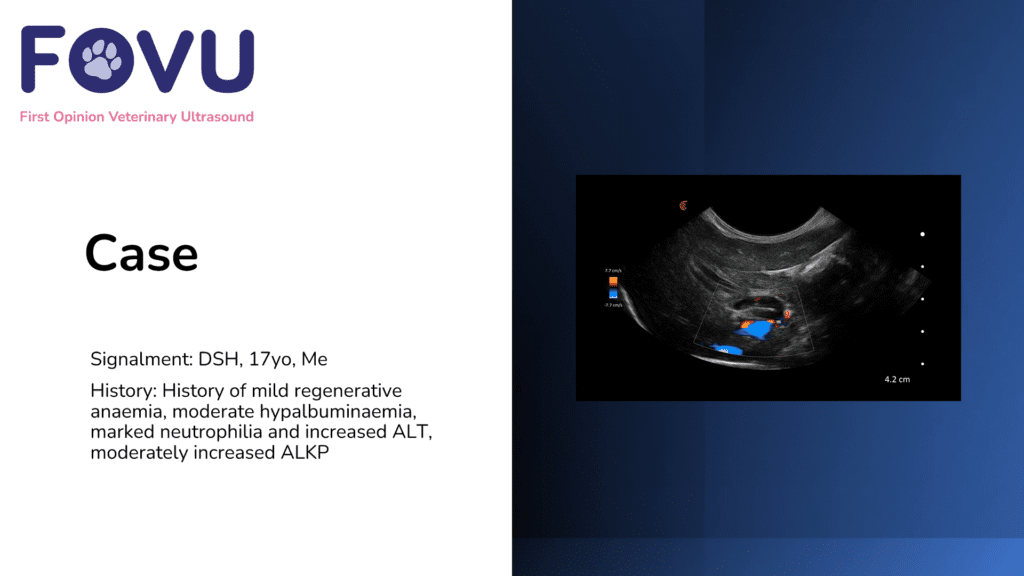

Small amount of free fluid in the abdomen (diaphragmatico-hepatic view) suggests an AFAST score 1/2.